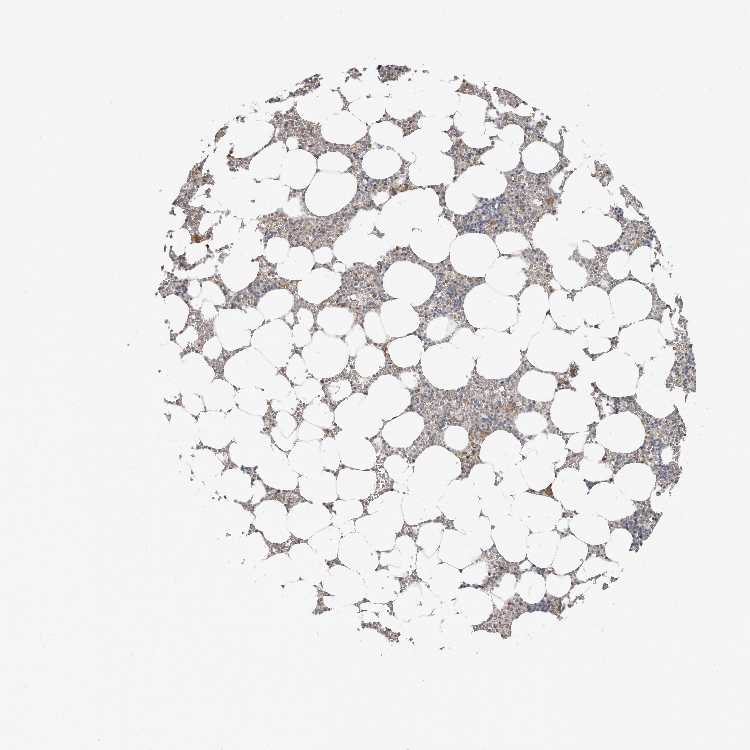

TISSUE PRIMARY DATA BONE MARROW Show tissue menu

BONE MARROW - Antibody stainingi

Antibody staining in the annotated cell types in the current human tissue is reported as not detected, low, medium, or high, based on conventional immunohistochemistry profiling in selected tissues. This score is based on the combination of the staining intensity and fraction of stained cells.

Each image is clickable and will lead to virtual microscopy that enables deeper exploration of all samples and also displays staining intensity scores, fraction scores and subcellular localization as well as patient and tissue information for each sample.

Antibody HPA027896Antibody HPA027897Antibody HPA027898

Hematopoietic cells MediumMediumMedium